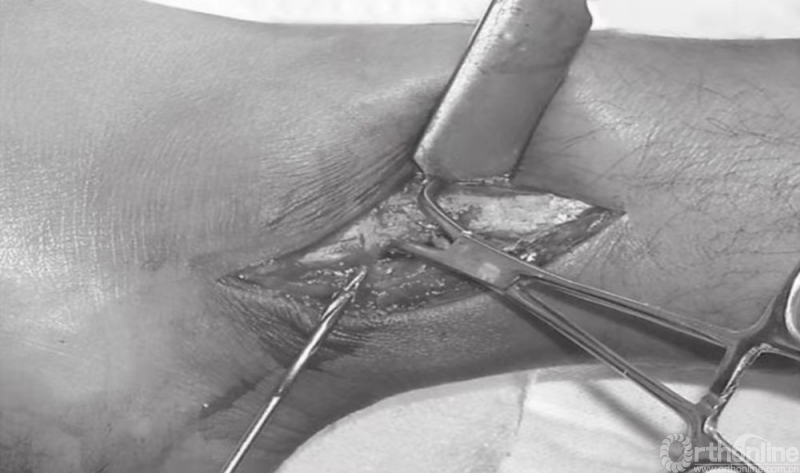

清理骨折末端软组织后,借助小复位钳将骨折片复位(图4)。解剖复位和腓骨长度的保持,尤为重要。除了腓骨的长度之外,也应检查旋转的方向。腓骨的短斜形骨折可用一枚拉力螺钉和一块中和接骨板加以固定(图5~8)。

图4 小复位钳将骨折片复位